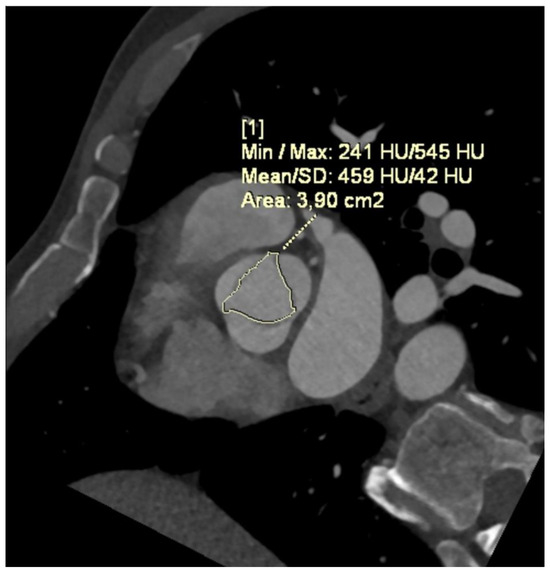

- Angelillis, M.; Costa, G.; De Backer, O.; Mochi, V.; Christou, A.; Giannini, C.; Spontoni, P.; De Carlo, M.; Sondergaard, L.; Miccoli, M.; et al. Threshold for calcium volume evaluation in patients with aortic valve stenosis: Correlation with Agatston score. J. Cardiovasc. Med. 2021, 22, 496–502. [Google Scholar] [CrossRef] [PubMed]

- Cartlidge, T.R.; Bing, R.; Kwiecinski, J.; Guzzetti, E.; Pawade, T.A.; Doris, M.K.; Adamson, P.D.; Massera, D.; Lembo, M.; Peeters, F.; et al. Contrast-enhanced computed tomography assessment of aortic stenosis. Heart 2021, 107, 1905–1911. [Google Scholar] [CrossRef] [PubMed]

- Flores-Umanzor, E.; Keshvara, R.; Reza, S.; Asghar, A.; Rashidul Anwar, M.; Cepas-Guillen, P.L.; Osten, M.; Halankar, J.; Abrahamyan, L.; Horlick, E. A systematic review of contrast-enhanced computed tomography calcium scoring methodologies and impact of aortic valve calcium burden on TAVI clinical outcomes. J. Cardiovasc. Comput. Tomogr. 2023, 17, 373–383. [Google Scholar] [CrossRef] [PubMed]

- Pandey, N.N.; Sharma, S.; Jagia, P.; Gulati, G.S.; Kumar, S. Feasibility and Accuracy of Aortic Valve Calcium Quantification on Computed Tomographic Angiography in Aortic Stenosis. Ann. Thorac. Surg. 2020, 110, 537–544. [Google Scholar] [CrossRef] [PubMed]